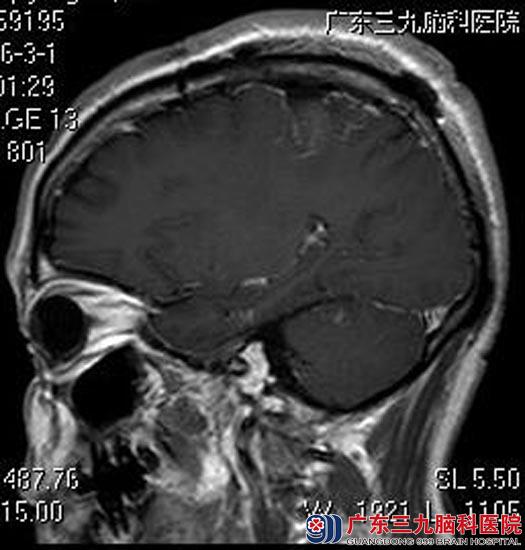

综合神经外科鲁明主任主刀在全麻下行右侧额顶叶脑膜瘤切除术,显微镜下见肿瘤质中偏硬,稍偏黄色,肿瘤一侧紧贴矢状窦,血供丰富,先电灼、分离肿瘤基底部,然后部分肿瘤,再分块分离切除肿瘤。肿瘤包膜完整,大小约5cm×5cm×4cm。最后分离、切除左侧术腔内残留肿瘤,手术顺利。术后刘先生的左下肢抽搐症状消失。术后病理结果提示:脑膜皮细胞型脑膜瘤(WHO I级)。